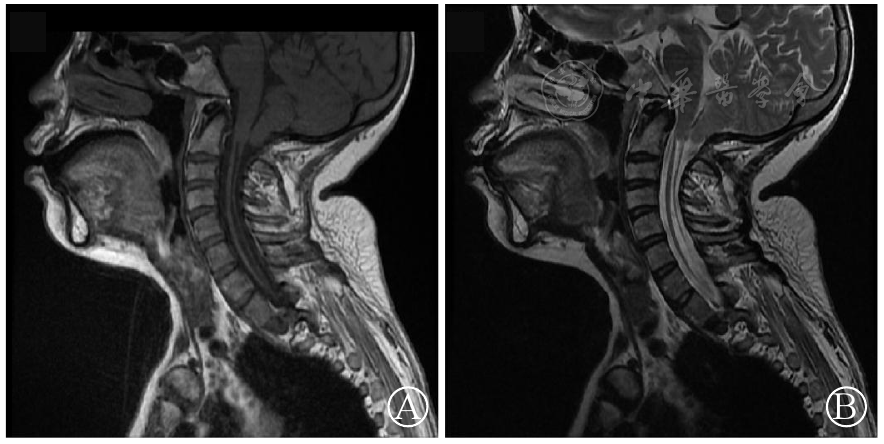

图2 颈椎MRI:小脑扁桃体下缘变尖,小脑扁桃体及延髓下段向下疝入枕骨大孔以下2 cm,脊髓空洞形成,Chiari畸形并脊髓空洞 图A:T1加权图像;图B:T2加权图像